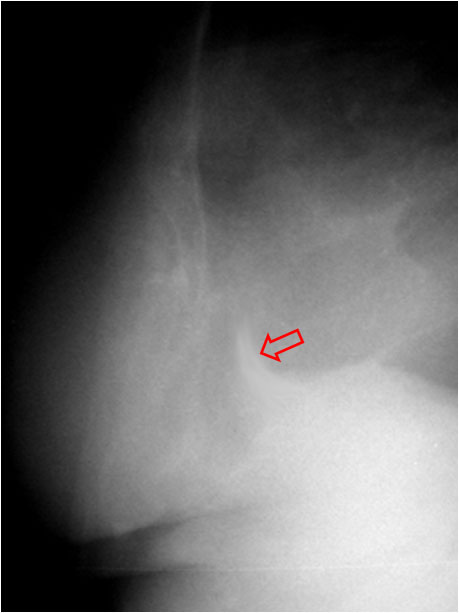

En la radiografía lateral de tórax, se ha descrito que la ausencia de la imagen del arco aórtico puede ser la clave diagnóstica de coartación aórtica. La imagen izquierda muestra el signo. Se trata del mismo paciente del Signo de las muescas costales (ver Otros signos de pleura/pared). La imagen derecha corresponde a una radiografía normal con la sombra aórtica visible (flecha).

Se han propuesto varias explicaciones para este signo; puede ser debido a hipoplasia del arco aórtico combinada con la coartación, a dilatación de las arterias braquiocefálicas (particularmente la arteria subclavia izquierda) que oscurecen el margen superior del cayado, o a hipoplasia y desplazamiento anteromedial de la porción distal del arco aórtico.